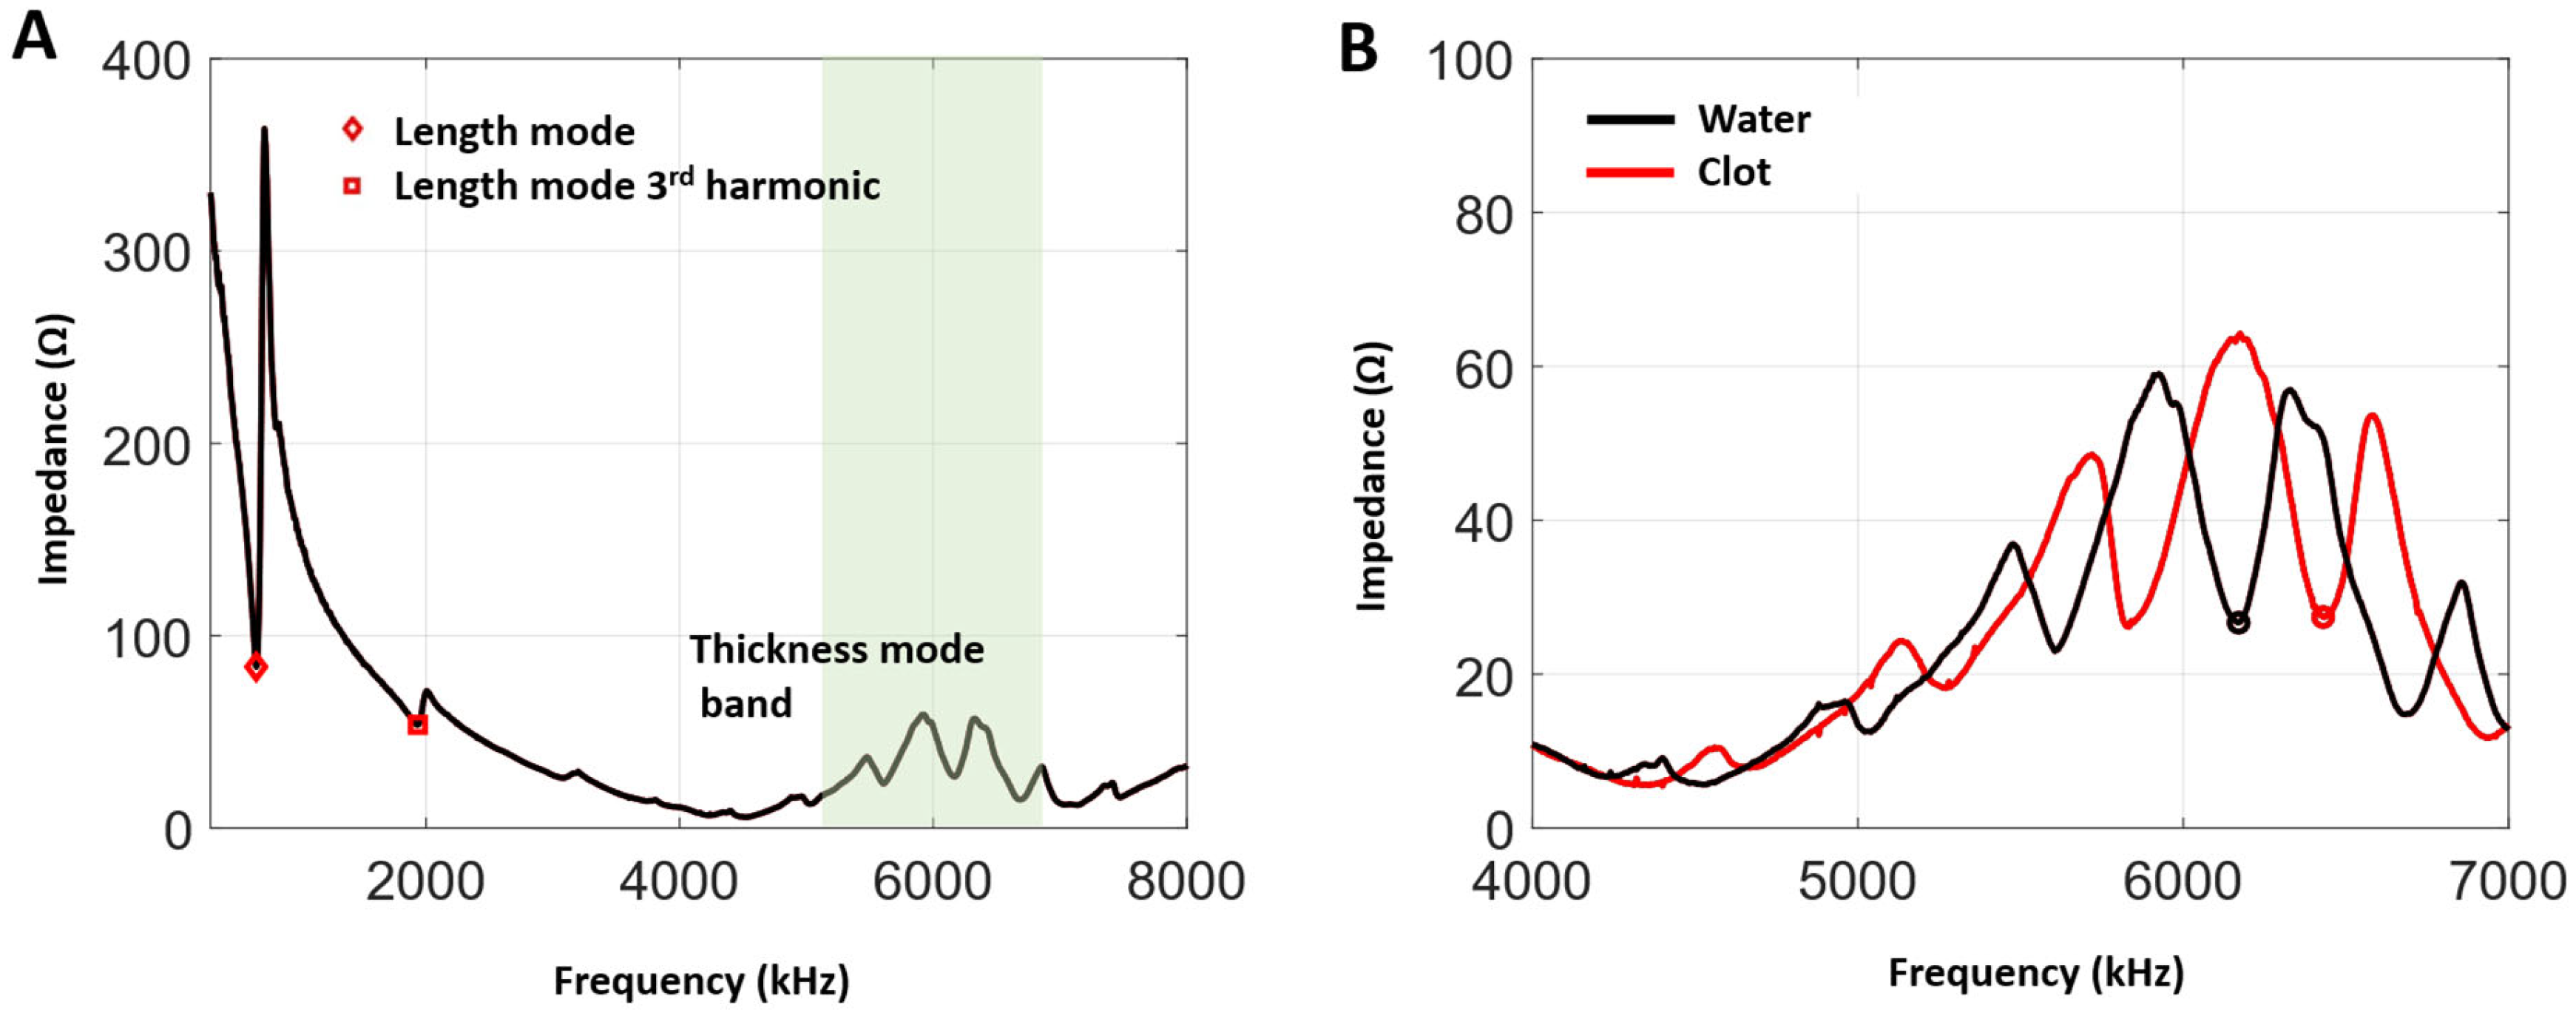

3.1. Impedance and Frequency Selection

2.2.2. Transmit Frequency Selections